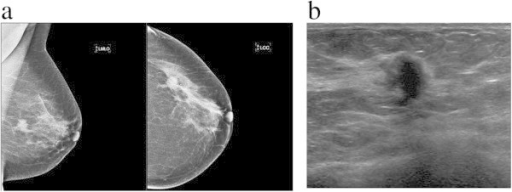

Lump or thickening

Lumps or thickened tissue can occur anywhere in the breast, including up to the collarbone and in the axilla. Breast lumps can present differently in different patients, e.g. they may be hard, soft, painless, painful, fixated, mobile, near the skin’s surface or deep in the breast tissue. A lump can also present as a thickened area of breast tissue that feels different from the rest of the breast.